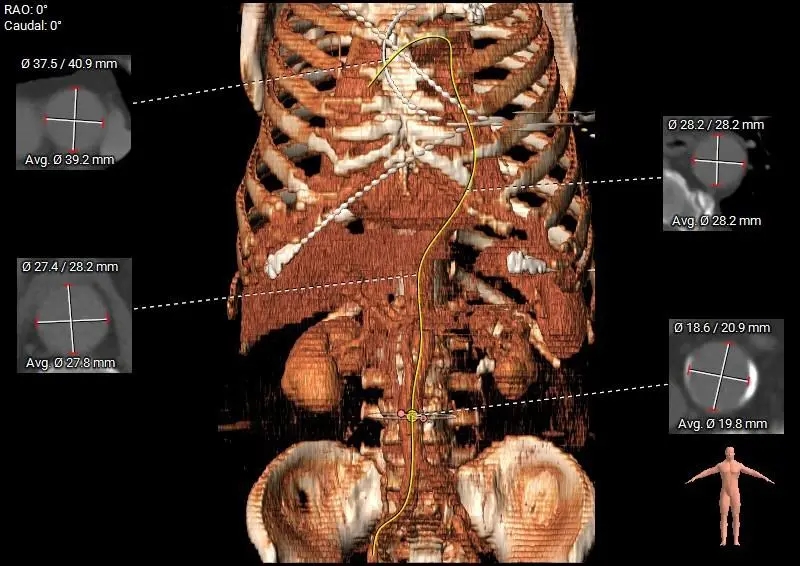

主动脉根部测量

周长径28.8

周长径29.5

L:48.2 N:47.3 R:24.8

周长径45.4

周长径45.5

L:28.1 N:27.3 R:24.5

瓣上结构测量

周长径28.6

周长径29.9

周长径31.5

周长径33.8

周长径35.4

周长径35.8

-

瓣上空间逐渐增大,瓣上瓣叶轻微增厚,0-6mm可提供锚定力

外周入路评估

外周血管无明显病

66°横位心

瓣膜型号:ScienCrown TAVTF32mm(oversize11.1%)

入路选择:经心尖入路(患者横位心,根部明显扩张故选择心尖入路)